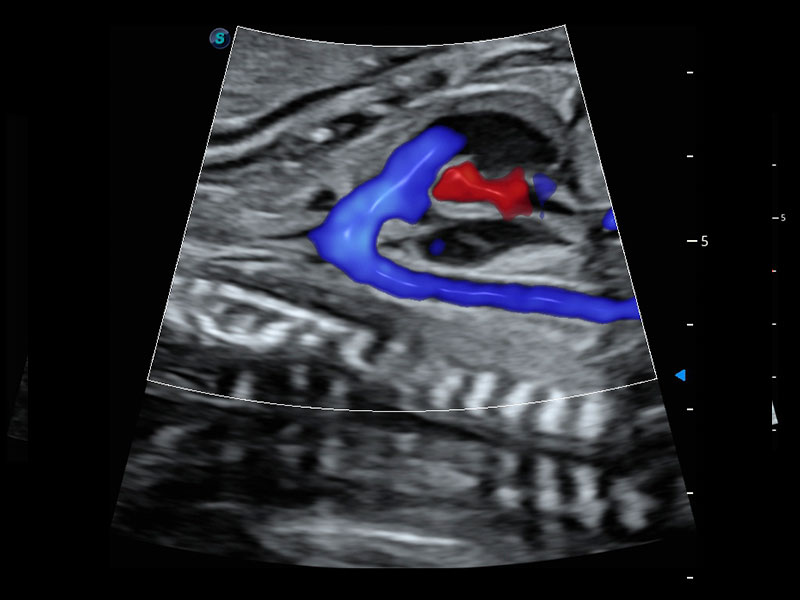

4D HyCoSy mit SPI

Die farbkodierte Hysterosalpingo-Kontrastsonografie (HyCoSy) ist eine proprietäre Funktion auf P60 Exp, die die Ankunftszeit von Kontrastmitteln in verschiedenen Teilen der Gebärmutter, der Eileiter und der Eierstöcke klar demonstrieren kann. Dadurch erhalten Kliniker starke und zuversichtliche Beweise, um die Tubenpatenz bei subfertilen Frauen zu untersuchen.

• Eileiter mit 4D HyCoSy

• Eileiter mit 4D HyCoSy mit SPI